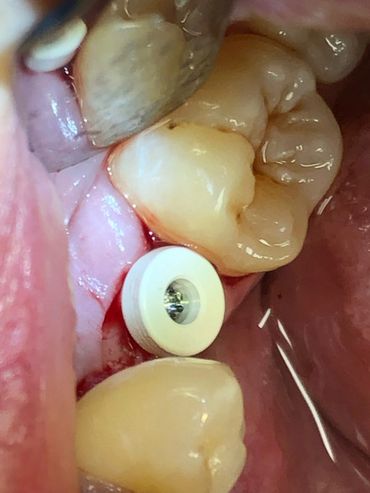

The Neodent® EasyGuide Sleeve is selected according to mesiodistal space and implant diameter.

During digital planning, sleeve positions must be assessed to avoid impact

Neodent® EasyGuide offers two sleeve diameters for optimizing positioning